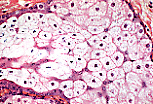

| 皮脂腺腔内可见两种细胞:腺细胞(皮脂腺细胞)和分隔细胞。 皮脂腺细胞的成熟过程从周边向中心及腺口方向推进:胞质中逐渐积累脂滴,使细胞呈透亮状;随着脂滴体积增大,中央的细胞核固缩退化;最终整个皮脂腺细胞被排出(全浆分泌)。此外还可见星芒状的分隔细胞,此类细胞不积累脂滴。 | |

| 此放大视图解释了皮脂腺细胞为何被称为海绵细胞:脂滴呈非融合性包涵体,在石蜡包埋过程中被溶解,使细胞呈现海绵状外观。 | |